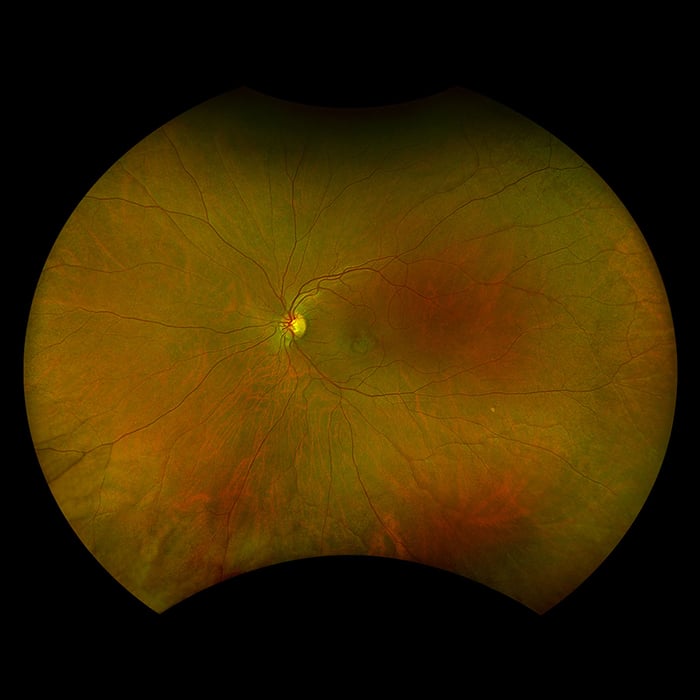

Optos a développé l'imagerie rétinienne dotée d'une technologie de laser à balayage ultra-grand champ (UWF™) afin d'obtenir une photographie du fond d'œil qui aide les praticiens à diagnostiquer, analyser, documenter et suivre les pathologies oculaires susceptibles d´être présentes en premier lieu dans la périphérie. Sans la technologie UWF™, les pathologies de la périphérie peuvent passer inaperçues lors de l’utilisation des techniques d’examen et des équipements traditionnels. Optos propose plusieurs appareils d'imagerie ultra-grand champ à haute résolution, générant des images simultanées sans contact allant du pôle à la périphérie pour visualier plus de 80 % ou 200˚ de la rétine en une seule prise, sans désagrément pour le patient.

Silverstone RGB redéfinit l’excellence dans l’imagerie rétinienne. Seul équipement capable de produire des images optomap ultra grand champ à 200° en une seule prise, parfaitement intégrées à un OCT swept-source guidé. Pour la première fois, les professionnels de la vue ont accès à neuf modalités d'imagerie performantes dans un seul système, chacune étant conçue pour visualiser les pathologies où qu'elles se trouvent sur la rétine.

Il est démontré que l’optomap améliore la détection, la prise en charge des pathologies ainsi que le flux des patients. Maintenant disponible avec neuf modalités d’imagerie, y compris un OCT Swept-source intégré, Silverstone RGB facilite l'examen de la rétine du vitré jusqu’à l’interface choroïdo-sclérale.

Modalités d'images et options de visualisation proposées par Silverstone RGB :

Modalités d’image optomap

- Couleur rgb

- Couleur rg

- anérythre (rétine sensorielle)

- choroïdienne

- af vert

- af bleu

- fa

- icg

- OCT-SS